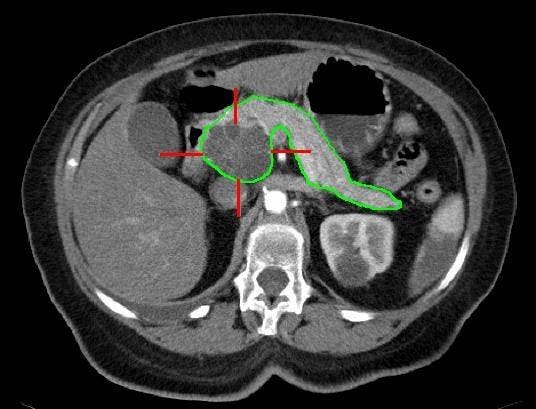

The unique characteristics of pancreatic tumors, such as dense tissue walls and abnormal blood vessels, make it difficult for immune cells to penetrate and target the cancer effectively. Additionally, the lack of clear targets on cancer cells and the similarity between healthy and cancerous cells pose further obstacles for immune cell therapy. As a result, traditional CAR T approaches have not been as successful in treating pancreatic cancer compared to other cancers.